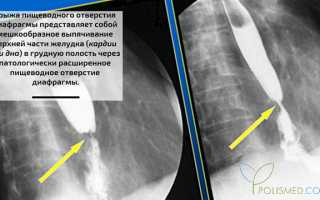

Грыжа пищеводного отверстия диафрагмы — это выпячивание верхней части желудка (кардии или дна) в грудную полость через расширенное пищеводное отверстие диафрагмы. Такие грыжи составляют 2–5% всех зарегистрированных грыж и относятся к внутренним, где грыжевой мешок проникает в полости организма.

| Рентгенологические методы(простая и контрастная рентгенография и рентгеноскопия) | * выявление хиатальных грыж; * дифференциальная диагностика с другими заболеваниями грудной клетки. | Исследование проводится натощак в вертикальном положении. Сначала выполняется снимок грудной клетки и брюшной полости для анализа тени пищевода и желудка, а также выявления патологий соседних органов. Затем пациент делает несколько глотков контрастного вещества (сульфата бария), что позволяет проследить его движение по пищеводу. После этого пациент выпивает больше контраста и принимает горизонтальное положение для рентгеноскопии или рентгенографии области желудка. Рентгенолог диагностирует грыжу пищеводного отверстия диафрагмы. |